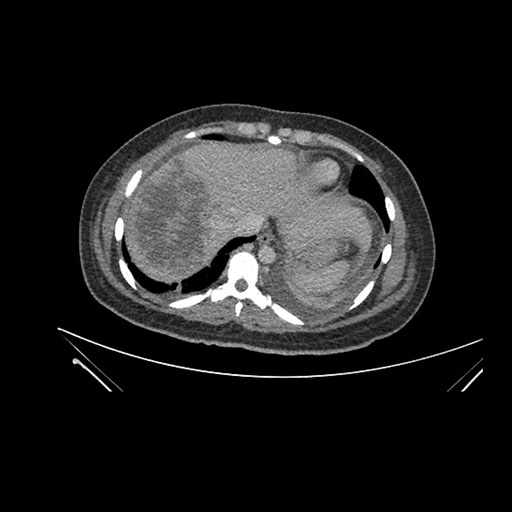

Imaging Analysis

Look through the patient's CT scan to identify any areas of concern for the necessary procedure.

Axial Venous

Based on initial findings, which issue(s) would you be most concerned about?